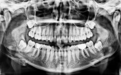

任何成功的手术都始于精密的术前规划。在种植牙领域,锥形束CT(CBCT) 是实现精准规划不可或缺的基石。它彻底告别了传统X光片的“平面猜谜”,能够提供您颌骨的三维立体影像,就好比为医生提供了一份您口腔的“透明地图”或“导航地图”。通过这份高精度的“地图”,医生可以:

精确评估“地基”条件:能够精确测量缺牙区牙槽骨的高度、宽度、密度,就像建筑师勘察土地一样,判断“土壤”是否肥沃坚实,是否满足种植条件,或是否需要先行植骨(“改良土壤”)。

安全规避“地下管线”:能清晰显示下牙槽神经管、上颌窦底、血管等重要解剖结构的位置。术前拍摄CBCT,能够了解口腔神经走向、血管分布、上额窦位置、牙槽骨状况等,是制定安全、精准手术方案的基石。这相当于在施工前就明确了所有地下管线的分布,从而在植入种植体时能够精准避开,极大提升了手术的安全性,从源头上避免了盲目操作可能带来的神经损伤、上颌窦穿孔等风险。